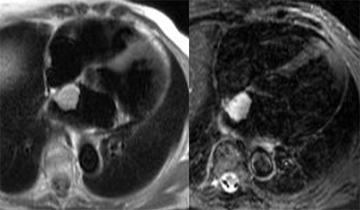

Récidive de rhadomyosarcome de la valve mitrale 6 mois apres resection tumorale et remplacement valvulaire mitral par une prothèse mécanique. Trois petites lésions punctiformes suspectes de métastases sont mises en évidence sur l’imagerie T1 post-gadolinium (flèches).

Récidive de rhadomyosarcome de la valve mitrale 6 mois apres resection tumorale et remplacement valvulaire mitral par une prothèse mécanique. Trois petites lésions punctiformes suspectes de métastases sont mises en évidence sur l’imagerie T1 post-gadolinium (flèches).